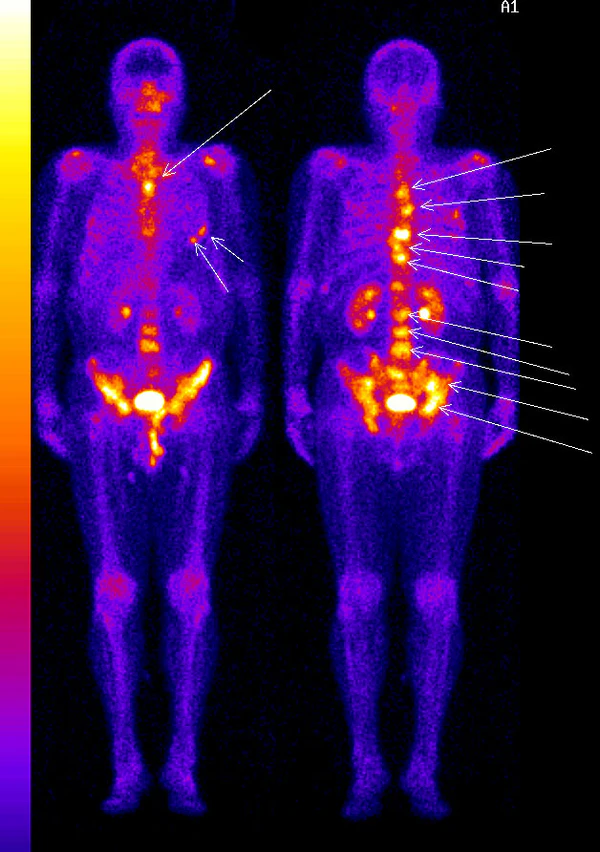

В настоящее время поиск метастазов в скелете — довольно сложная задача, где наиболее чувствительным и специфичным методом является сцинтиграфия остеотропными радиофармпрепаратами. Сцинтиграфические находки выглядят как единичные или множественные, равномерные — неравномерные, фотопенические или гепераккумулированные очаги и т. д.

Большинство костных метастазов соответствует распределению костного мозга в скелете и локализуется в осевом скелете (80 %[4]): позвоночник, таз, рёбра, грудина и череп. Соответственно до 20 % метастазов локализуется в конечностях или черепе, поэтому важно при проведении остеосцинтиграфии сканировать весь скелет.